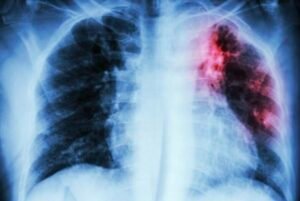

The Union calls for comprehensive TB screening in high-burden settings. 24 March,2024 On World TB Day 2024, the International Union Against Tuberculosis and Lung Disease (The Union) calls on all stakeholders, including multilateral agencies, governments, national and local programmes, non-governmental organisations, academics, activists and donors, to focus on activities that will break the chain of transmission in high-burden settings in order to end tuberculosis (TB).

In high-burden settings, TB is endemic: meaning everyone is at risk, all the time, through the unbroken chain of transmission. To break the chain it is critical that we screen everyone in high-burden settings for TB, so that we can find and treat all people with TB and prevent them from infecting others.

The latest evidence shows that in high-burden settings, most people with infectious TB do not have symptoms (such as, cough or fever) and many are not members of high-risk groups. Hence, it is vital that screening for TB is not limited to those with symptoms or those who are members of high-risk groups.During the height of the COVID-19 pandemic, before the availability of vaccines, this approach of widespread testing, was rolled out by governments across the globe and proved to be highly effective in controlling the spread of COVID-19.

In 2022, 10.6 million people fell ill with TB and 1.3 million died from the disease, more deaths than from any other infectious disease.Prof Marks explains: “The incidence of TB in high-burden countries is falling at a glacially slow pace. The simple reason for this is that far too many people with TB remain undiagnosed and untreated, often because they do not experience or recognise symptoms that lead to a diagnosis. These people are infectious and can transmit the infection to others in their households, workplaces and communities.